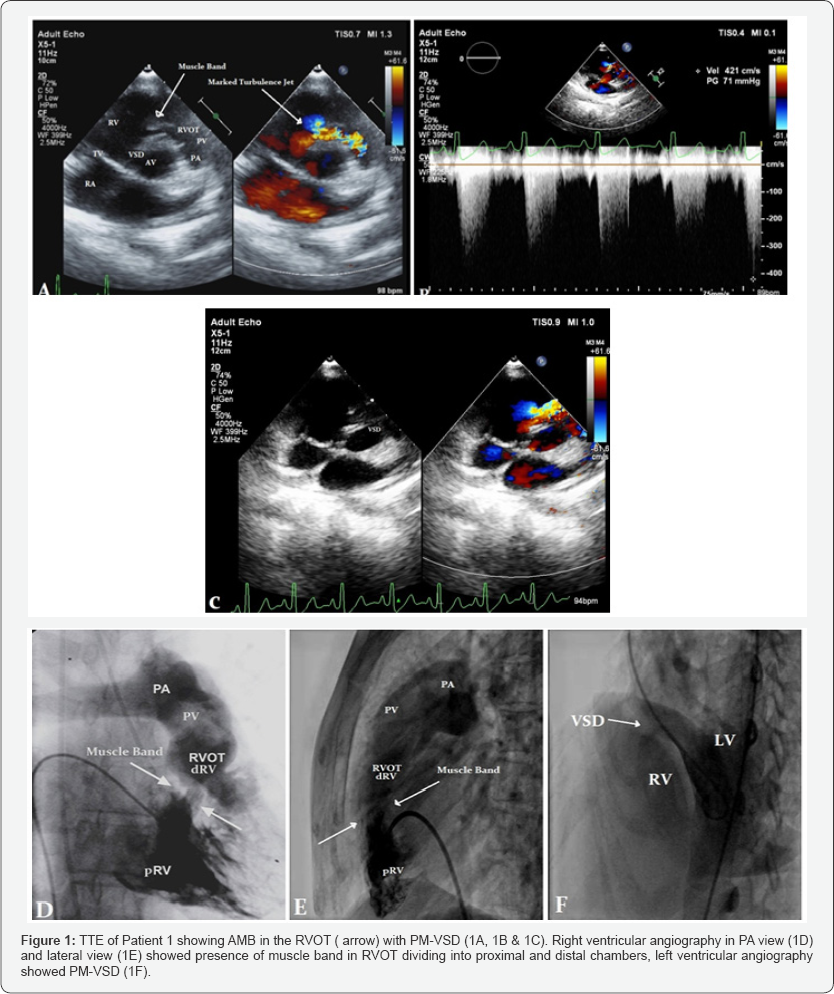

Two dimensional (2D) imaging with doppler assessment by color and continuous wave doppler done to know the site of flow turbulence and quantification of gradients across AMB. Trans-esophageal echocardiography (TEE) confirmed the Trans-thoracic echocardiography (TTE) findings. Right and left- heart catheterization was carried out in all patients. Both Right ventricle and Left ventricle outflow gradients were recorded. Pull back pressure gradient recorded from the pulmonary artery to the right ventricular outflow to the right ventricular inflow. Right ventricular angiography was done in both antero-posterior and lateral view and left ventricular angiography done in Left anterior oblique view.

All patients underwent detailed echocardiography, pulmonic valve was normal in all patients. Cardiac catheterization and catheterization was done in all patients, Figure 1 showing cath of Patient 1. Figure 1-3 showing echo findings of patient 1, 2 & 3. Echocardiography and catheterization findings are shown in Table 2.